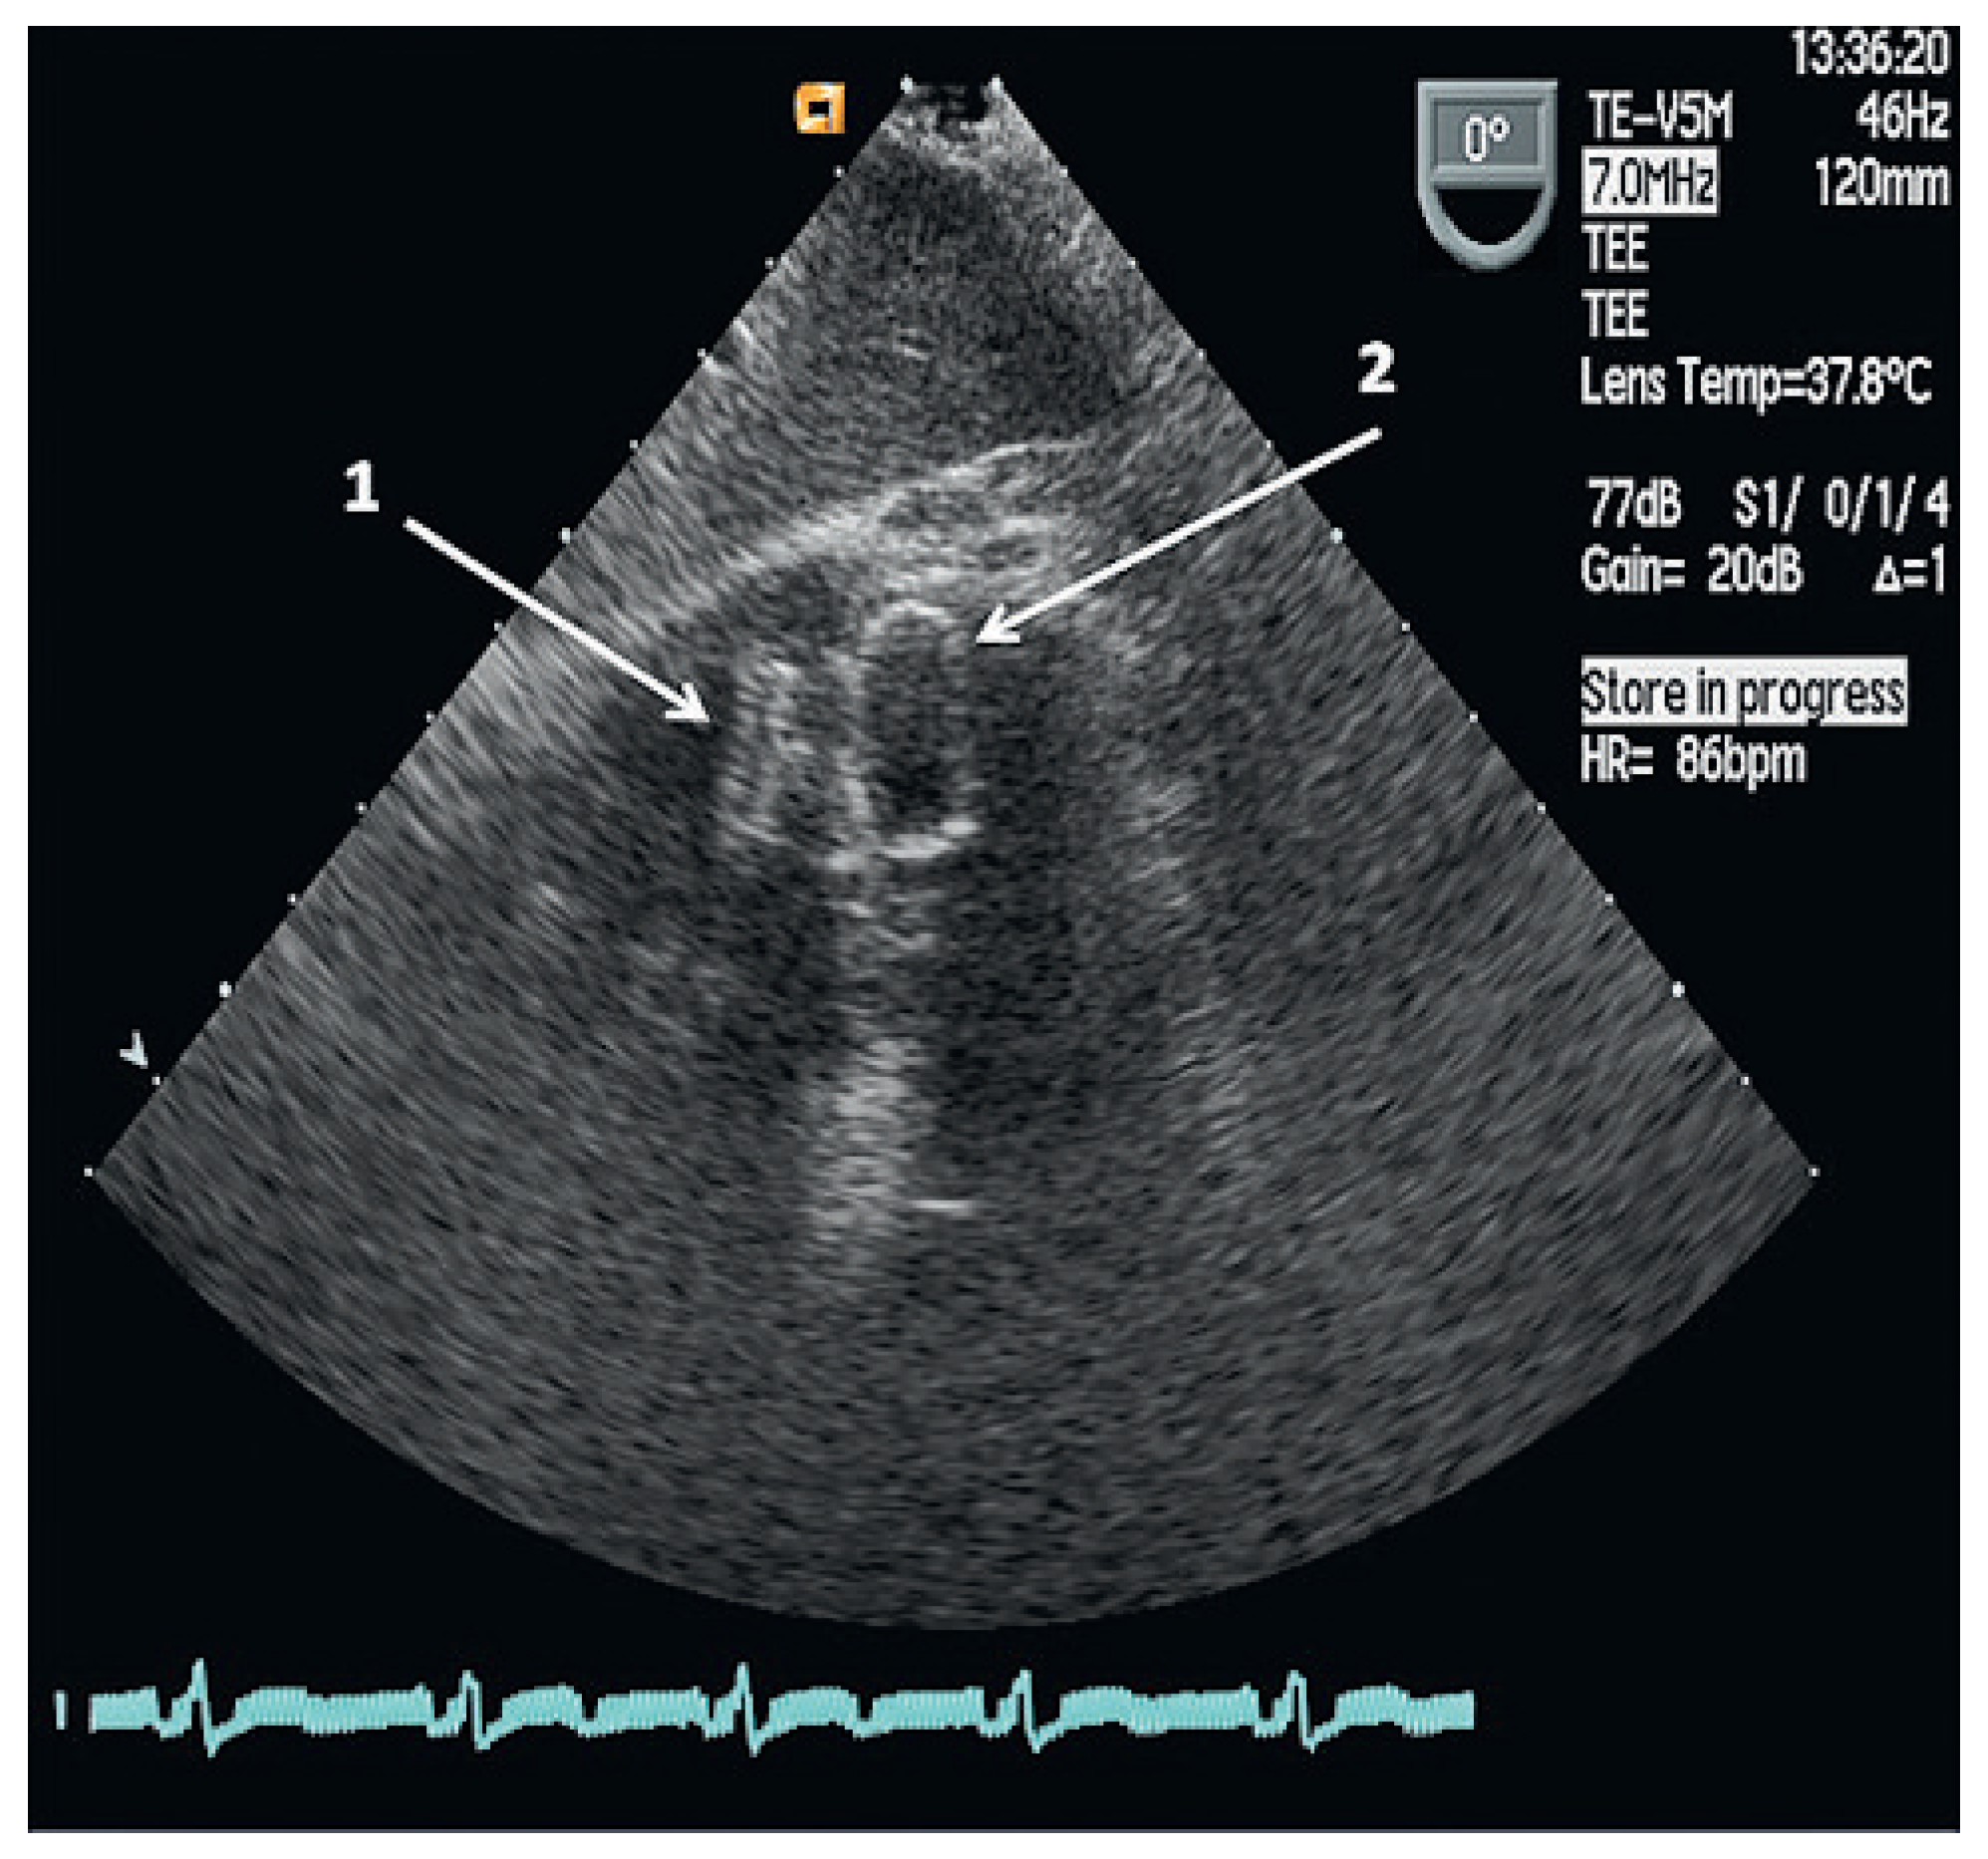

The residual VSD was identified with left ventricular contrast injection and the defect was crossed from the left ventricular side using a guide wire which was snared in the pulmonary artery and exteriorized thus creating an arteriovenous loop. The VSD was measured using a 34 mm sizing balloon (St. Jude-AGA) (Figure 1). A 14 mm Amplatzer muscular VSD occluder (St. Jude-AGA) was implanted through an 8 F TorqVue sheath (St. Jude-AGA) inserted through the right femoral vein (Figure 2). Adequate position was confirmed under fluoroscopy with contrast injection into the left ventricle (Figure 3). The procedure was performed without TEE and under local anaesthesia.

Figure 1. Measurement of the apical VSD by means of a sizing balloon (34 mm). LV (left ventricle), RV (right ventricle), VSD (ventricular septal defect).